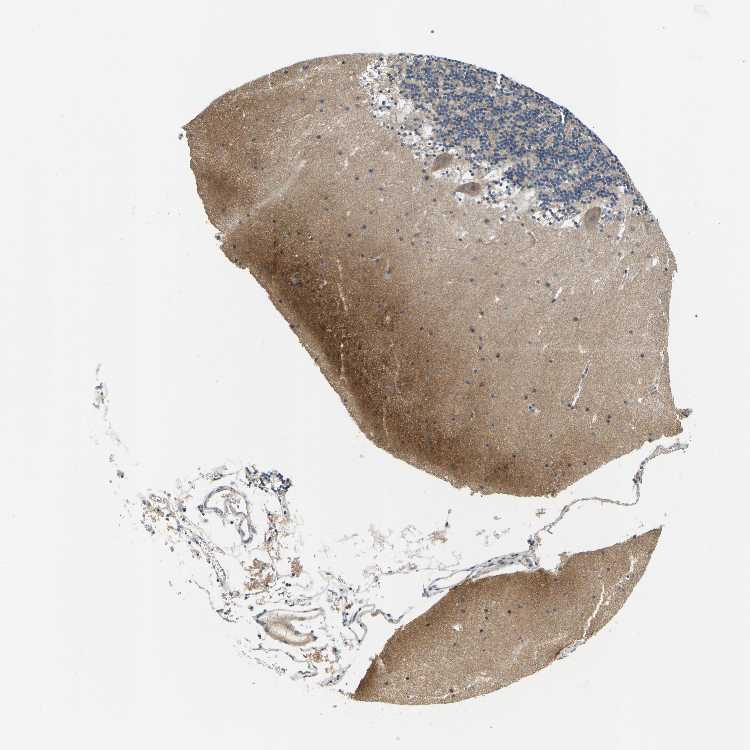

BRAIN CEREBELLUM Show tissue menu

CEREBELLUM - Expression summary

CEREBELLUM - Antibody stainingi

Antibody staining in the annotated cell types in the current human tissue is reported as not detected, low, medium, or high, based on conventional immunohistochemistry profiling in selected tissues. This score is based on the combination of the staining intensity and fraction of stained cells.

Each image is clickable and will lead to virtual microscopy that enables deeper exploration of all samples and also displays staining intensity scores, fraction scores and subcellular localization as well as patient and tissue information for each sample.

Antibody HPA012016Antibody CAB000276Antibody CAB025522

Purkinje cells LowNot detectedLow

Cells in granular layer MediumLowLow

Cells in molecular layer LowNot detectedHigh